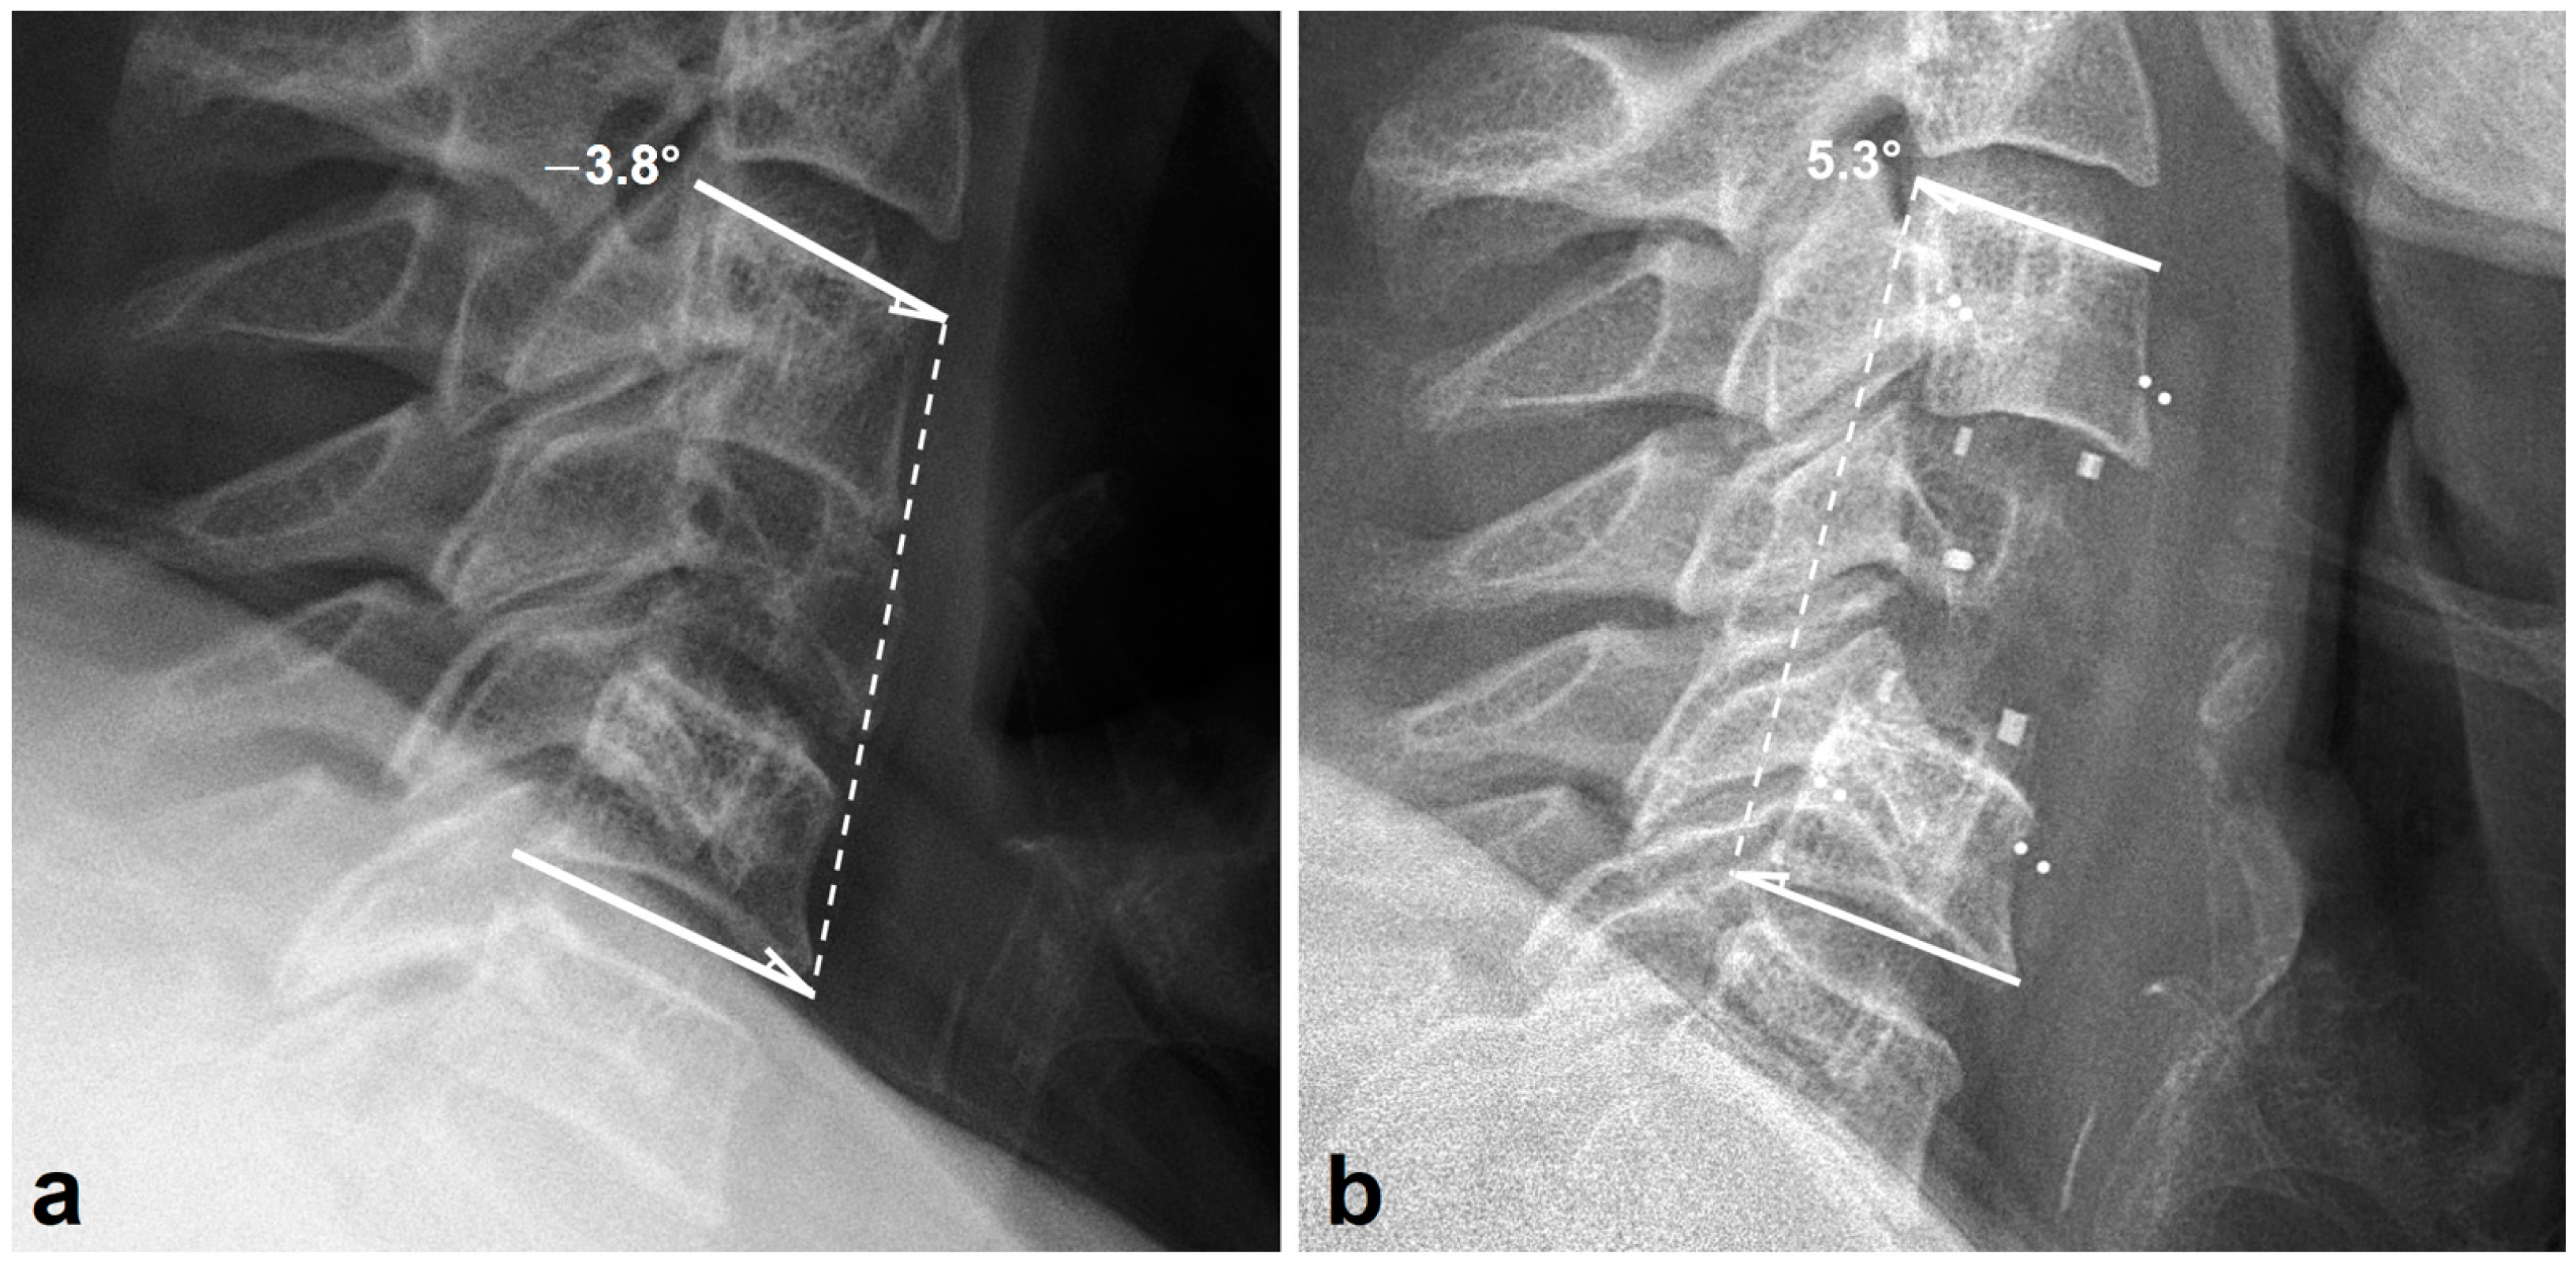

2.3. Radiologic Outcome

3.2. Radiologic Outcomes